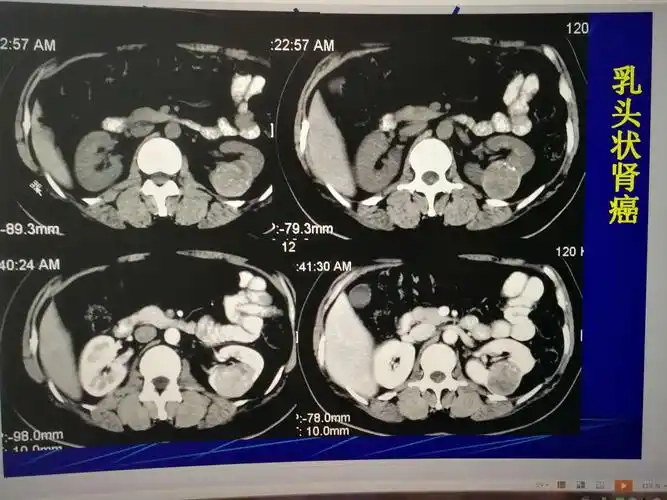

汉寿县人民医院泌尿外科成功进行一例腹腔镜下左肾癌根治术

肾肿瘤的ct诊断与鉴别诊断!

ct:左肾癌肾癌是泌尿外科常见的疾病,我见过最年轻的成年人肾癌患者是